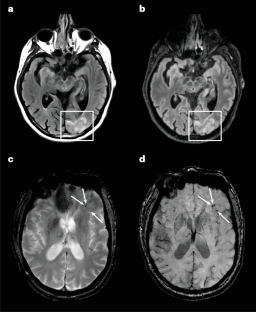

Sharifi, K. J. et al. The use of portable MRI in the detection and monitoring of amyloid-related imaging abnormalities. Alzheimers Dement. 21, e104467 (2025).

Okafor, J. P. N. et al. Advanced imaging modalities for ARIA detection and treatment efficacy monitoring in lecanemab therapy for Alzheimer’s disease: a collaborative prospective study. Alzheimers Dement. 20, e095167 (2024).

Hampel, H. et al. Amyloid-related imaging abnormalities (ARIA): radiological, biological and clinical characteristics. Brain 146, 4414–4424 (2023).

Cogswell, P. M. et al. Amyloid-related imaging abnormalities with emerging Alzheimer disease therapeutics: detection and reporting recommendations for clinical practice. Am. J. Neuroradiol. 43, E19–E35 (2022).